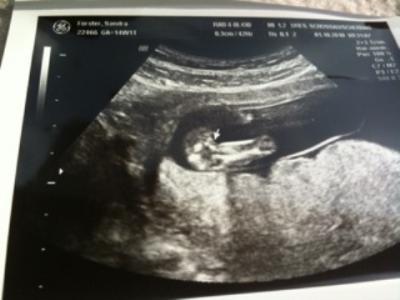

Huhu, war heute bei der VU und es ist allles bestens :-) habe zwar noch wegen der Blutungen die ich 4 Wochen lang hatte Sex- und Sportverbot, aber was macht man nicht alles ;-) Wir haben auch ein 95%iges Outing bekommen, ein Mädchen anbei auch das Beweisfoto, wobei ich ehrlich sagen muss, ich sehe da nichts Die Kleine ist 8,3 cm groß und war total aktiv, ganz die Mama :-) Heute habe ich die Kleine auch wieder gespürt, ist schon toll, wenn man es nicht nur auf den US-Bildern sieht, sondern jetzt so wirklich auch langsam spürt, dass da was in einem ist Gruss Sandra

Bild zu Heute VU und ein 95%iges Outing - Forum für März - Mamis